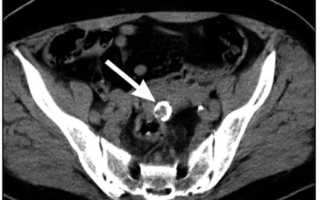

| Диагностика | УЗИ, КТ, МРТ. | Визуализация кальцификатов в миоме на изображениях. |

Для диагностики данного типа новообразований используются те же методы, что и для обычных опухолей. Тем не менее, ультразвуковое исследование может столкнуться с определенными трудностями. Кальцинированные опухоли иногда сложно идентифицировать на УЗИ, особенно если они небольшие.

Более четкие результаты можно получить только при наличии узлов диаметром от 8 мм, так как они кальцинируются довольно редко. Обычно наличие таких новообразований на УЗИ определяется по гиперэхогенным включениям с акустическим эффектом.